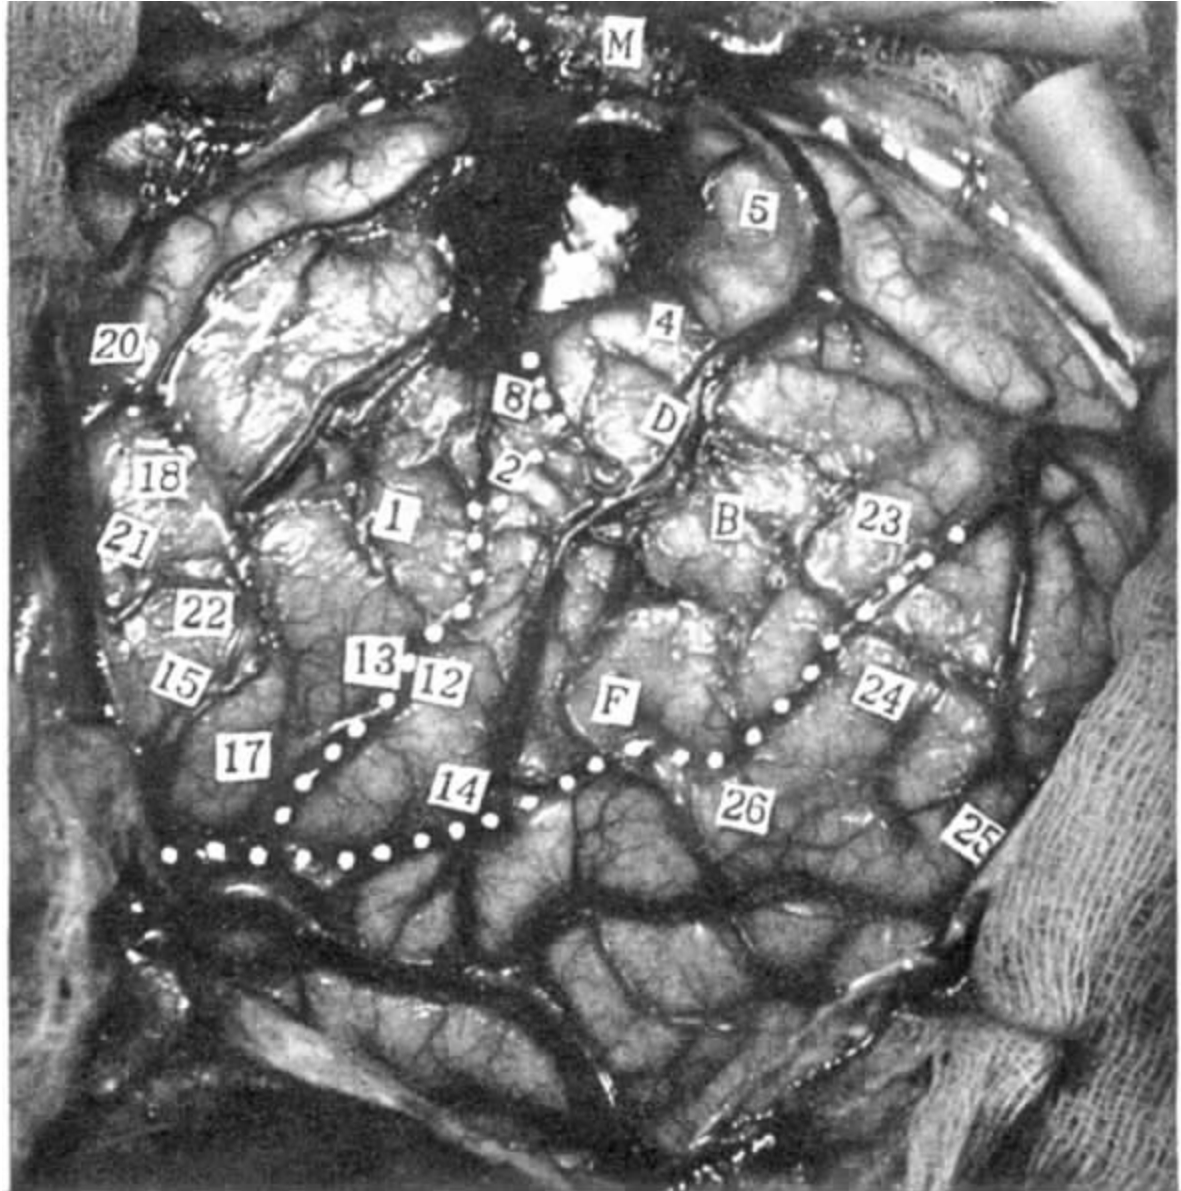

病例2 A.Br.

局灶性癫痫,精神性错觉,害怕,不自主动作,腹鸣。脑刺激引起患者听到音乐。

病人的癫痫发作与右侧颞叶前部下表面的局灶性病变有关,可能是病人1岁时发热性血栓性大脑静脉炎所致。

发作由她的一些思想波动启动。她感到自己好像在另一个世界,感到害怕,可能紧接着不自主动作和遗忘症,持续15分钟。发作接近结束时,可清晰听到腹鸣音。

右侧开颅手术。

电刺激部位

右脑,近中央沟和外侧裂处(见图6-2)。

电刺激脑的反应及特点

某些刺激的结果看来与记忆有些关系,陈述如下:

17 “我仿佛听到了一首歌,熟悉的那种,就像在听收音机。”

18 “是的,一瞬间我感到害怕。”她解释说这是她发作时伴有的那种害怕。

21 刺激点位于颞叶底部。病人说:“是的,就像我过去感觉到的中魔一样。”这个刺激在大约10秒钟的电记录抑制后。“我好像失去了对思想的控制,我看见的任何东西好像都要离开,很不寻常。”然后她加了句话,她不能把这些幻觉用语言表示。

图6-2 病例A.BR.图中所标数字为有刺激反应的位置(刺激17、18、24和点25使患者感觉听到歌;刺激点21,使患者丧失对思维的控制)

24 她说:“不,”然后说:“我想起了一首歌,但我不知道这是什么歌。”

18 重复。她说,这使她努力想象一首熟悉的歌。不是她听到了音乐。

24 没有提醒下重复。她说这使她想起一首歌。该刺激每次都产生一次小的后放电。

4 拇指麻刺感。